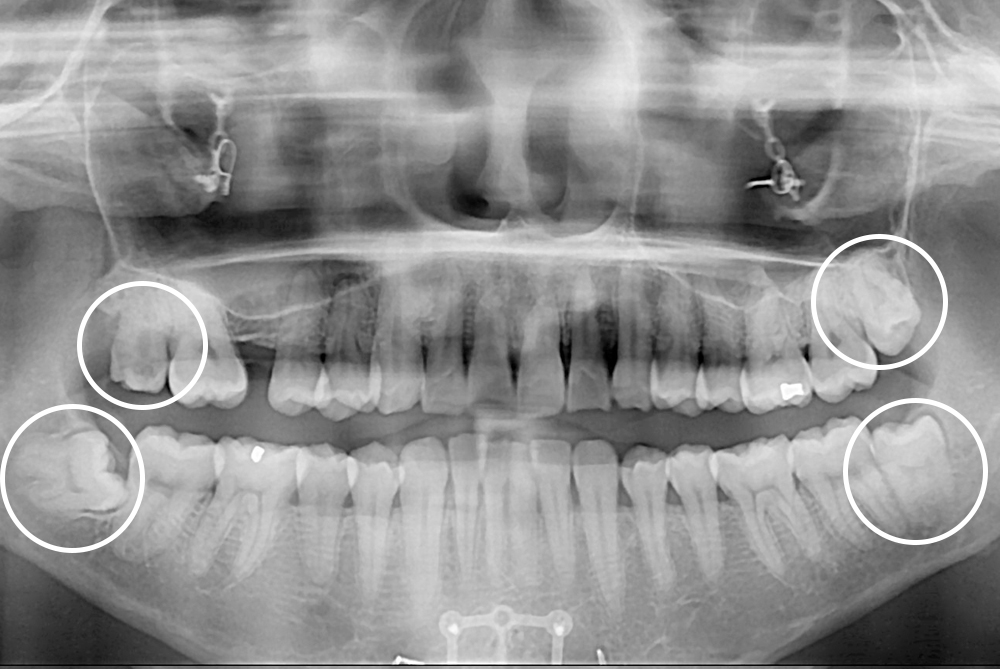

[사랑니] 매복 사랑니 발치

치료후 : 2021-04-12

세종치과는 구강악안면외과학 박사이신 원장님이 발치하는 치과입니다.